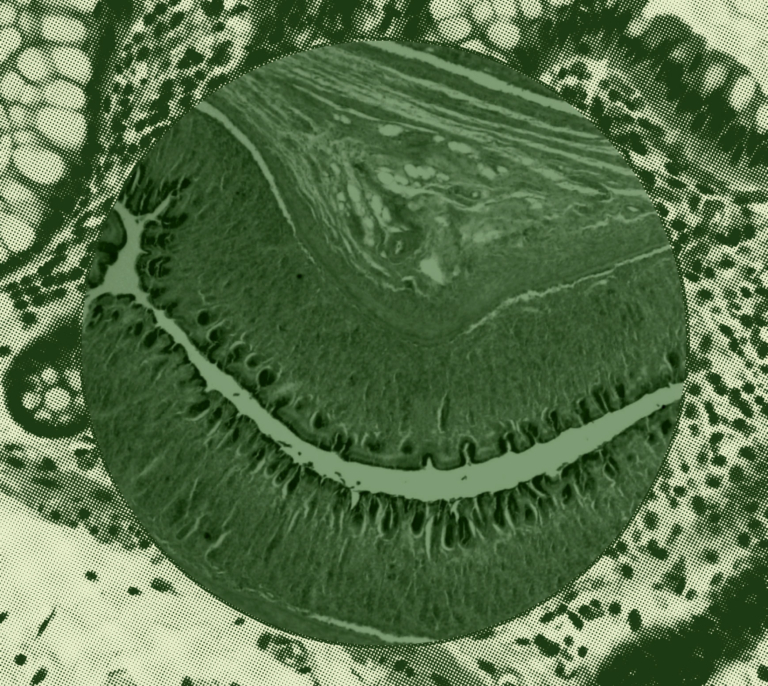

Why Is Gut Barrier Integrity Important?

3 minutes